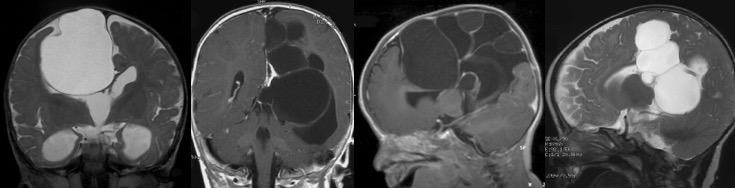

les kystes arachnoïdiens de diagnostic anténatal

la prévalence des différentes localisations est différente en pré et en post-natal :

ceci confirme que les kystes arachnoïdiens sont des pathologies développementales, apparaissant à des âges différents suivant la topographie.